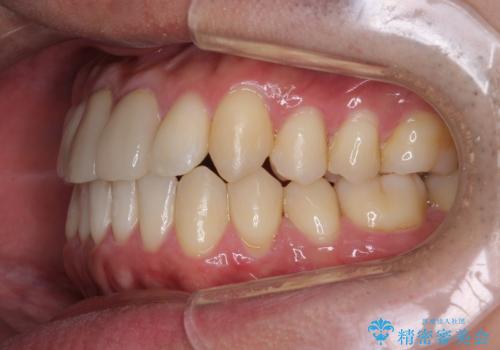

上下のがたつきをインビザラインで目立たない矯正

目立たずに歯並びがよくなり、前歯に装着されたセラミックも壊さずに矯正治療が終了し満足していただけました。

- 前歯のガタガタを主訴に来院されました。

上下の前歯のガタガタと左上の歯が反対にかんでいる状態でした。